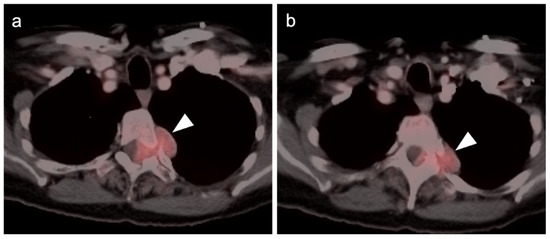

- Kayani, I.; Conry, B.G.; Groves, A.M.; Win, T.; Dickson, J.; Caplin, M.; Bomanji, J.B. A Comparison of 68Ga-DOTATATE and 18F-FDG PET/CT in Pulmonary Neuroendocrine Tumors. J. Nucl. Med. 2009, 50, 1927–1932. [Google Scholar] [CrossRef] [Green Version]

- Zidan, L.; Iravani, A.; Kong, G.; Akhurst, T.; Michael, M.; Hicks, R.J. Theranostic implications of molecular imaging phenotype of well-differentiated pulmonary carcinoid based on 68Ga-DOTATATE PET/CT and 18F-FDG PET/CT. Eur. J. Pediatr. 2020, 48, 204–216. [Google Scholar] [CrossRef]